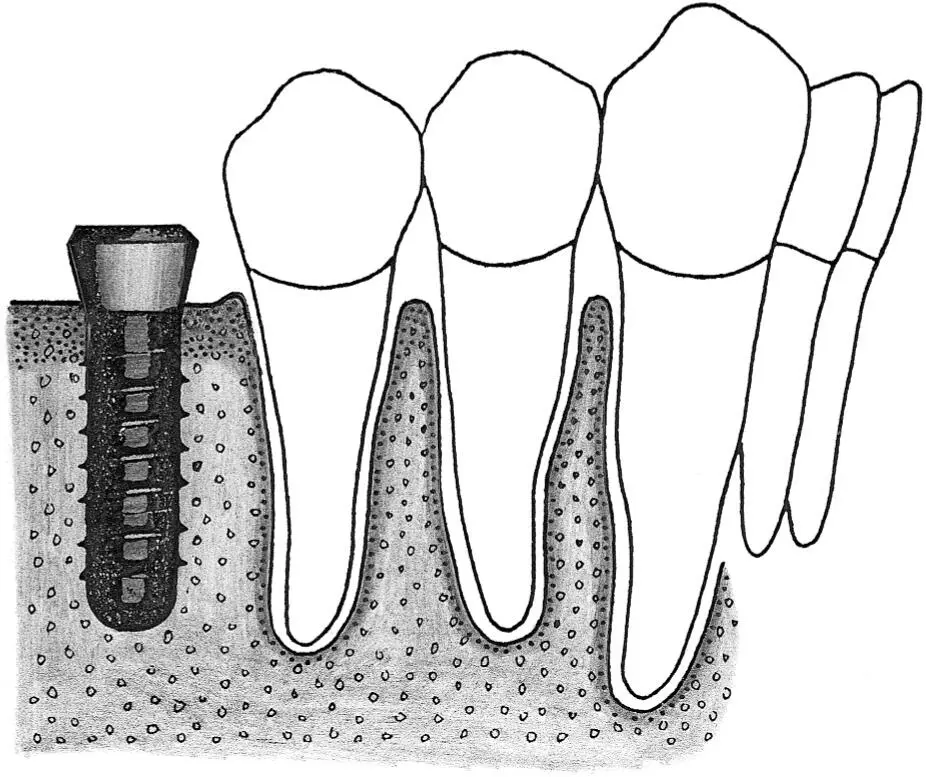

Fig 1-1Smoothing the alveolar crest following flap elevation.

Fig 1-1a Once the implant surgical site has been exposed, a large round bur is used to smooth and level the crest of the alveolar ridge.

Fig 1-1b All sharp edges and irregularities are removed by running the round bur across the alveolar ridge.

Fig 1-1c In this cross section, the irregular, narrow crest is smoothed to produce a flat, wide ridge, which is favorable for implant site preparation.